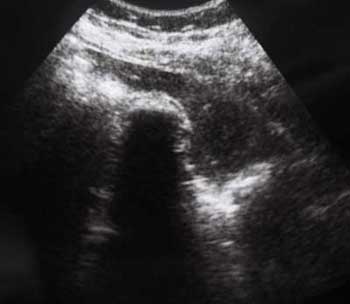

Похожий случай сегодня: